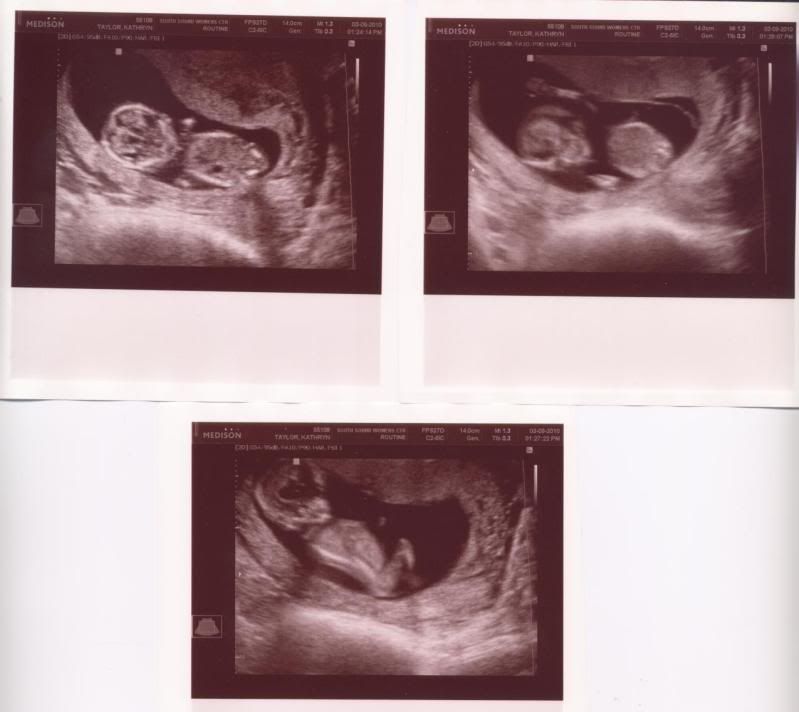

So last Tuesday I had a little scare (symptoms I wasn't expecting) and we went to the Doctor's for an Ultrasound. The baby was swimming around like crazy and it's heart was beating...so they said we were just fine! Thank goodness. Here's a picture at 12 weeks 6 days:

Wow! S/he looks like a real baby!